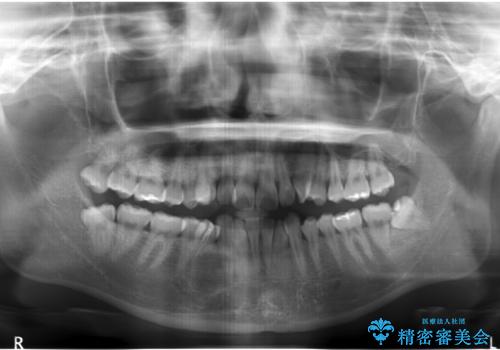

- 前歯のねじれを主訴に来院。

レントゲンを撮影したところ、右下4は神経のない歯で、外部吸収といって、根がだんだん短くなり、やがて抜けてしまう症状になっていました。また、アンキローシスを起こしている可能性があるため、動かない可能性が高い状態でした。

矯正治療で右下を抜歯し、スペースを天然の歯でつめる矯正治療を行いました。

治療期間はかかりましたが、右下4が一生もつとは思えない状態でしたので、人工物を入れないようにすることができました。

矯正治療をしない場合は、右下はブリッジかインプラントが必要になっていたと思います。